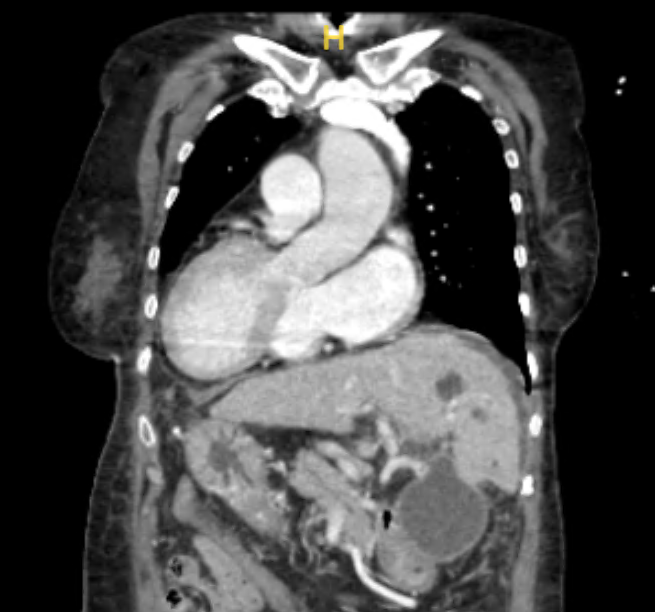

▲术前影像学检查显示,患者心脏位于右侧,肝脏位于左侧

但令医院肝移植团队谨慎的是,赵阿姨是一位全内脏反位患者。全内脏反位带来的解剖变异对脉管重建的影响如同“左脚穿右鞋”,这给手术团队带来了不小的挑战。